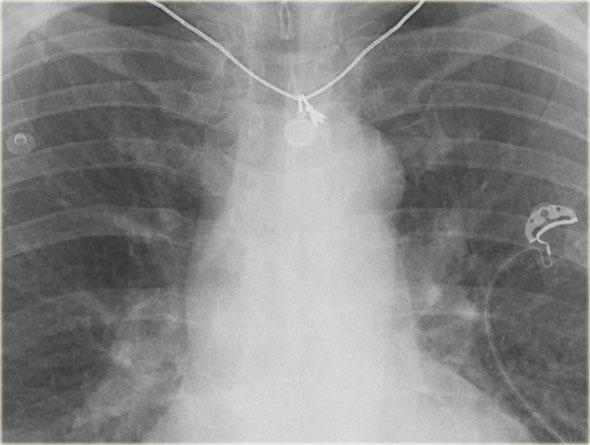

Hình ảnh bên trái là của một bệnh nhân có các dấu hiệu của suy tim sung huyết (CHF).

Thoạt nhìn, bạn có thể có ấn tượng rằng cơ hoành đang ở vị trí cao.

Tuy nhiên, khi nhận thấy khoảng cách tăng lên giữa bóng hơi dạ dày và đáy phổi, bạn sẽ nhận ra rằng có một lượng lớn dịch màng phổi ở cả hai bên (mũi tên).